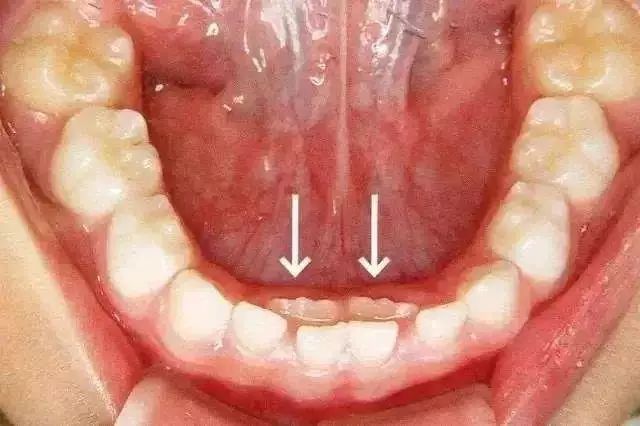

最近看到好几个群里的妈妈在探讨孩子的牙齿问题,其中一个妈妈发了一张照片,询问大家:孩子的恒牙貌似有一点点冒出的迹象,但是恒牙还没掉,这情况咋办!

因为从小吃够了牙齿的苦,所以就像公号里很早和大家分享牙齿科普知识一样,我对OK口腔健康一直是比较重视的。一方面因为刷牙开始得很早、刷的时候也保质保量,一方面他可能遗传了爷爷良好的牙齿基因,所以乳牙虽然也有黑色素沉淀,但没有任何蛀牙。可就是没想到,OK换牙时出现了双排牙(当时没拍)。我在网上找了下面这张图,就是类似这种情况,乳牙还在原位,但是下面恒牙已经冒出头来了,看起来还挺滑稽。

当时请教了牙医好朋友,我是等着乳牙脱落呢,还是带OK去医院看看。好朋友给出的建议是,你看看他的乳牙松动了没,如果松动了,自己可以掉下来,那就可以再观察等等看,那几天可以给点苹果玉米啃啃,看看乳牙能否掉下来。如果乳牙虽然松了,但自己依然不掉,恒牙又冒出更多,那还是要去看医生、拔乳牙,给恒牙挪位置的,要不然恒牙一直没有机会在正确的位置上成长,之后的牙齿很难长得整齐!

“哦,还有这等事?”爷爷也是有点意外,“那看来回去还得跟他奶奶说说!”“对,现在这种双排牙的问题特别多,基本上我们碰到的10个小朋友至少5个有这种情况存在,主要就是吃得太精细。妈妈也要记住,就比如苹果给孩子吃,就是洗干净了削个皮,让娃捏着整个一个,大口大口啃,牙齿才有机会锻炼!”